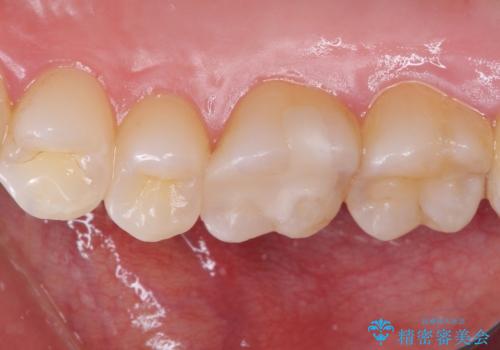

そして次の来院時、セラミックインレーを装着し、噛み合わせなどの調整を行います。

それを左右に分けて行いました。

インレーを装着するときは、唾液や血液による接着力の低下を避けるためにラバーダム防湿を行いました。

自然な色調で大変満足されました。